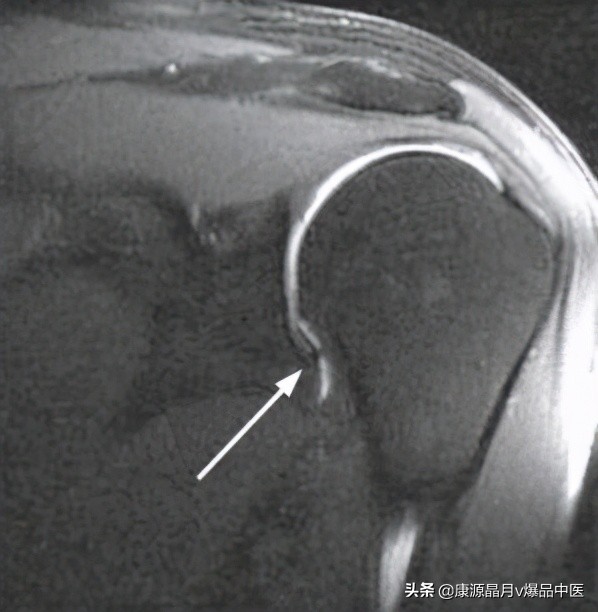

辅助检查拍摄肩关节正位和腋位片以确认肩关节间隙和对应关系是否正常,同时依此可以排除包括骨赘、游离体、钙化和肿瘤在内的其他病变。也可进一步行造影或磁共振造影等辅助性检查,在冻结肩患者会表现为关节囊的挛缩和腋囊的消失(图1)。

图1:肩关节冠状位MRI显示关节囊挛缩,同时下关节囊囊袋消失,而这成为冻结肩的特征。文献引用:Coronal shoulder MRI demonstrates the contracted capsule, which is the hallmark of a frozen shoulder, and the loss of the inferior pouch (arrow).